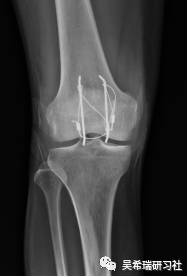

平台骨折手术后继发感染

TIPS:内固定感染常见病不要轻易做皮瓣,感染情况下不可深部骨感染、窦道用水泥切实可行多数皮肤没有缺损,肿胀消退后可以牵张闭合